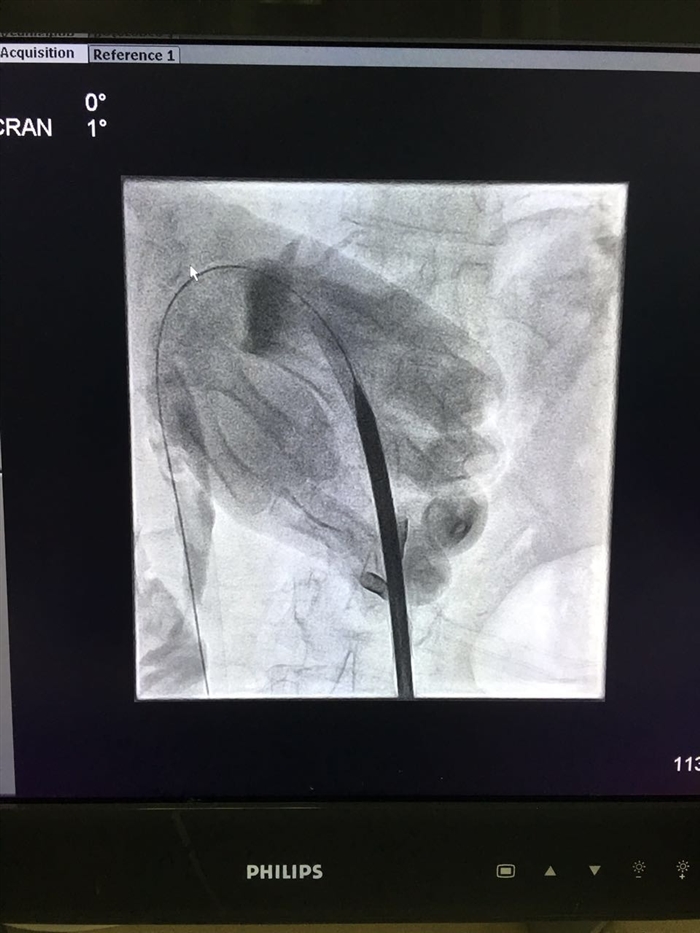

6月29日晚上7点,肝胆外科在龚建平主任指导下及泌尿外科姜庆主任的鼎力协助下,由留美归来的刘作金副主任主刀,程瑶博士为助手,历时4小时,为一例反复多次手术的肝内外充满型胆管结石伴严重肝硬化的患者成功完成了经皮经肝胆道造瘘联合经皮肾镜碎石取石术。该手术采用杂交手术的方式完成,先于B超下定位穿刺目标胆管,随后于介入中心逐次扩张胆管并置入合适直径外鞘。再将患者移入普通手术室在全麻下经扩张隧道用经皮肾镜碎石。此手术在西南地区尚属首例。术后患者病情稳定,于2016年7月6日恢复出院。

刘作金教授介绍,经皮经肝胆道造瘘后碎石取石术是一种新颖的微创手术,仅需在皮肤上打2-4个小孔就可以治疗各种复杂肝内外胆管结石。其原理与经皮肾镜手术十分相似。不过,肝脏因呼吸运动引起的动度比肾脏大,加上肝内的血管、胆管合并走行,手术的风险及难度远较比经皮肾镜要大,多需通过杂交手术方案协同完成。手术主刀医生同时要求具有熟练的B超穿刺及介入手术基础。